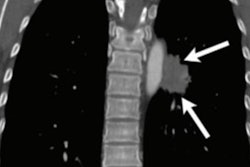

A group led by Olivier Gevaert, PhD, created a neural network called LungNet to gather lung cancer information from CT scans, particularly those from adults with non-small cell lung cancer (NSCLC), which represents the majority of diagnoses of the disease.

The group trained the network on four patient cohorts with NSCLC from four medical centers. LungNet accurately predicted overall survival in all four patient groups, accurately categorized benign and malignant nodules, and it further classified nodules according to cancer progression, according to the researchers.